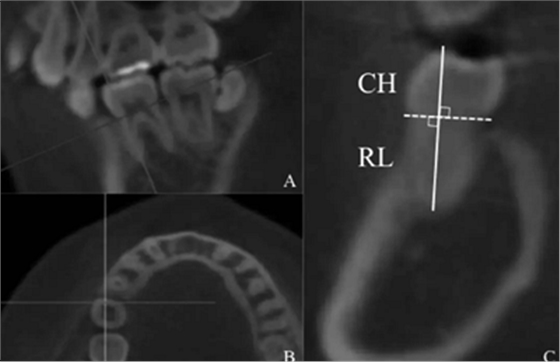

材料和方法:受試者包括193名日本成年人(69名男性,124名女性),年齡13至56歲。 使用Taqman基因分型從唾液和基因分型的GHR rs6184和rs6180變體中提取基因組DNA。 使用CBCT獲取計(jì)算機(jī)斷層掃描(CT)圖像,并使用OsiriX醫(yī)學(xué)圖像處理軟件重建。分別對(duì)上頜(上;U)和下頜(下,L)中切牙(1)、側(cè)切牙(2)、尖牙(3)、第一前磨牙(4)、第二前磨牙(5)、第一磨牙(6)和第二前磨牙(7)進(jìn)行了評(píng)估。評(píng)估這些牙齒的冠高(CH),牙根長度(RL),總牙長(C+R)和牙冠比(C/R)。并對(duì)GHR變體與CH、RL、CR R和C/R的關(guān)系進(jìn)行了統(tǒng)計(jì)學(xué)檢驗(yàn)。